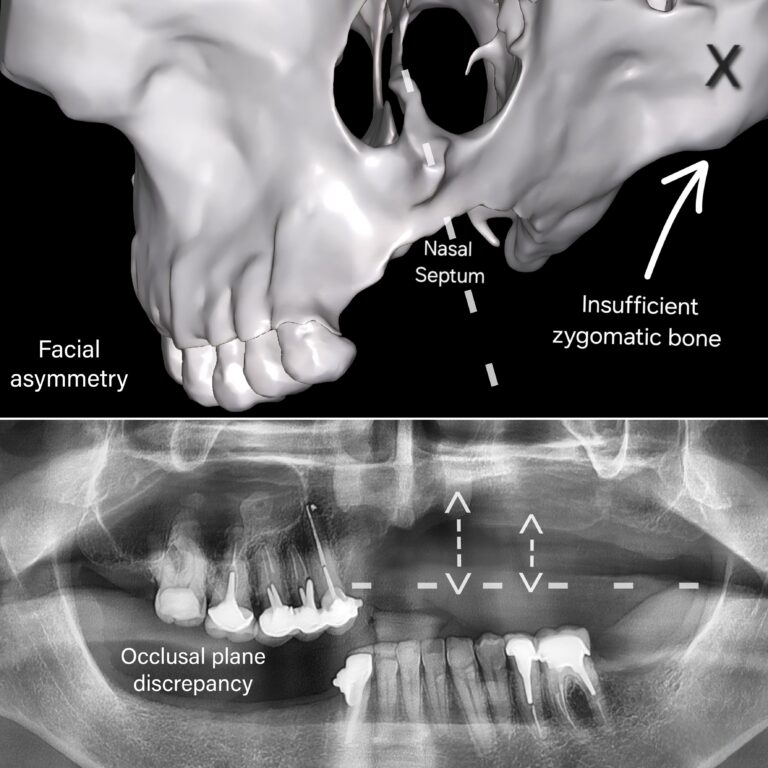

Severe bone atrophy with maxillary asymmetry

Baseline anatomical condition: 2D and 3D imaging revealing severe bone atrophy with maxillary asymmetry.

Three-dimensional radiographic analysis revealed a particularly critical anatomical situation.

In the left maxillary sector (sector 2), residual bone was virtually absent in the posterior regions. The alveolar ridge appeared extremely thin, with insufficient height and width to support conventional implant stabilization.

In contrast, the right maxillary sector (sector 1) exhibited a distinct configuration, resulting in marked asymmetry between the maxillary halves. This asymmetry was not only volumetric but also involved the position of the sinus cavities.

The prior trauma had significantly altered the osseous architecture, leading to asymmetric sinus pneumatization with sinus floors at different levels on each side.

Residual bone density was low, and the maxillary ridge was severely resorbed. Under these conditions, not only were conventional implants contraindicated, but extensive bone grafting strategies were also considered unrealistic, given both the anatomical alterations and the limited structural capacity of the recipient site.

A comprehensive analysis of the remaining cortical structures, zygomatic morphology, and asymmetric sinus constraints was therefore performed in order to identify stable and reliable anchorage zones.

Radiographic examination, however, revealed significant morphological asymmetry between the two sides.

The right zygomatic bone exhibited a relatively favorable architecture, with sufficient cortical thickness to allow reliable anchorage. In contrast, the left zygomatic bone appeared markedly thinner, with significant volumetric reduction, likely due to prior traumatic sequelae. This structural asymmetry considerably increased the complexity of implant planning.

As a result, zygomatic rehabilitation could not be approached using a standard bilateral protocol. Each side required a tailored strategy, adapted to the specific morphology and bone density of the respective zygomatic arch.

Despite these significant anatomical constraints, zygomatic implantology remained the only therapeutic option capable of providing a stable and durable fixed rehabilitation. This approach was guided by biomechanical considerations and the identification of reliable cortical anchorage, rather than by attempting an unpredictable reconstruction of an unusable maxillary bone.